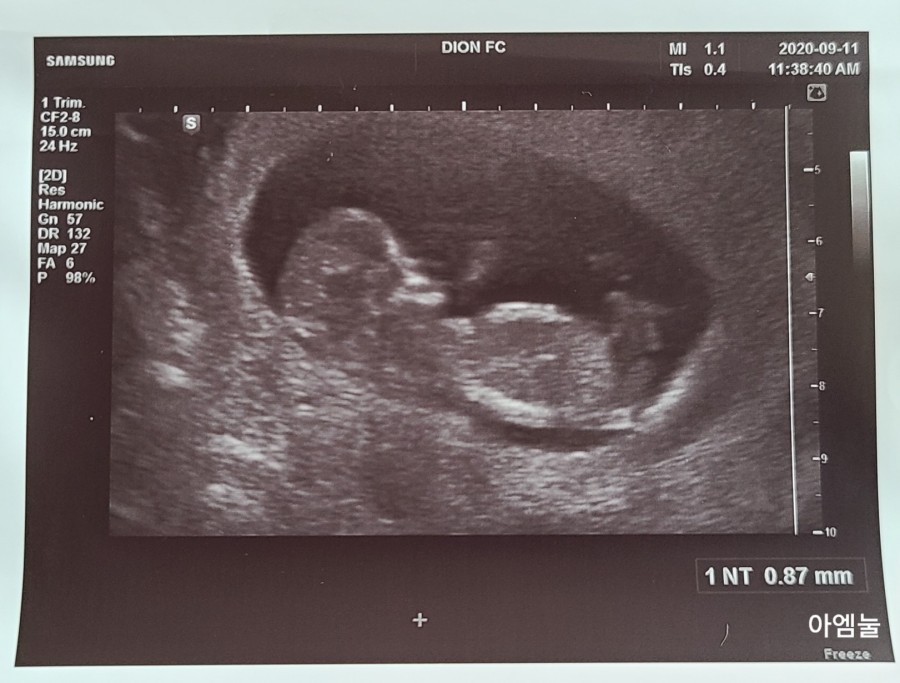

1차 기형아 검사 목투명대 검사! 3mm 이상이면 다운증후군이나 염색체 이상 위험이 있다고 하지만 봄에는 0.87mm로 정상이었습니다.